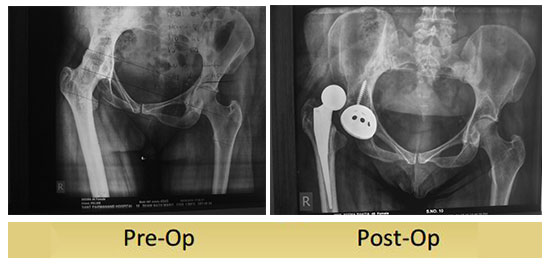

46 year old lady sequale of infective arthritis with fused hip underwent Uncemented Total Hip Replacement 2 months. She had postoperative dislocation of the hip joint. Managing post op dislocation after Total Hip Replacement is challenging and requires loads of clinical experience. Identifying the cause of dislocation is critical to prevent redislocation of hip joint.

Closed reduction under anaesthesia was not possible for this patient so we attempted open reduction . we revised the acetabular cup from conventional cup to Dual mobility cup to reduce redislocation .

Post operatively patient is comfortable and walking with walker.